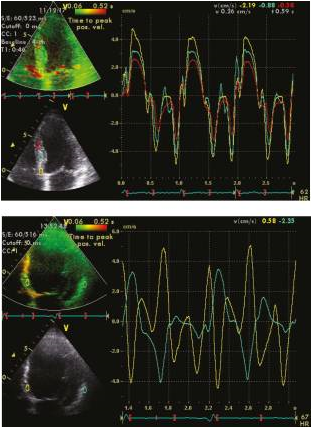

The introduction of myocardial velocity imaging dates back to the early 1990s, [51], [52] and since then, it has become a well-established method for quantifying both left ventricular (LV) systolic and diastolic function. Real-time imaging of myocardial motion allows for the visualization of color-coded velocities overlaid on a 2D grayscale image. The frame rate for 2D color Doppler typically ranges between 80 and 200 frames per second, depending on the sector width, and is usually set higher than that of simultaneous grayscale images. The analysis of myocardial velocities can be performed offline, as shown in [Figure 5].

Clinical application of tissue Doppler velocity imaging extends to various areas. It can be utilized for diagnosing myocardial ischemia, assessing patients with diastolic dysfunction, and aiding in the selection of suitable candidates for cardiac resynchronization therapy through the evaluation of ventricular dyssynchrony, as depicted in [Figure 6]. Tissue Doppler velocity imaging plays a crucial role in these clinical scenarios, providing valuable information for diagnosis, evaluation, and treatment decisions.